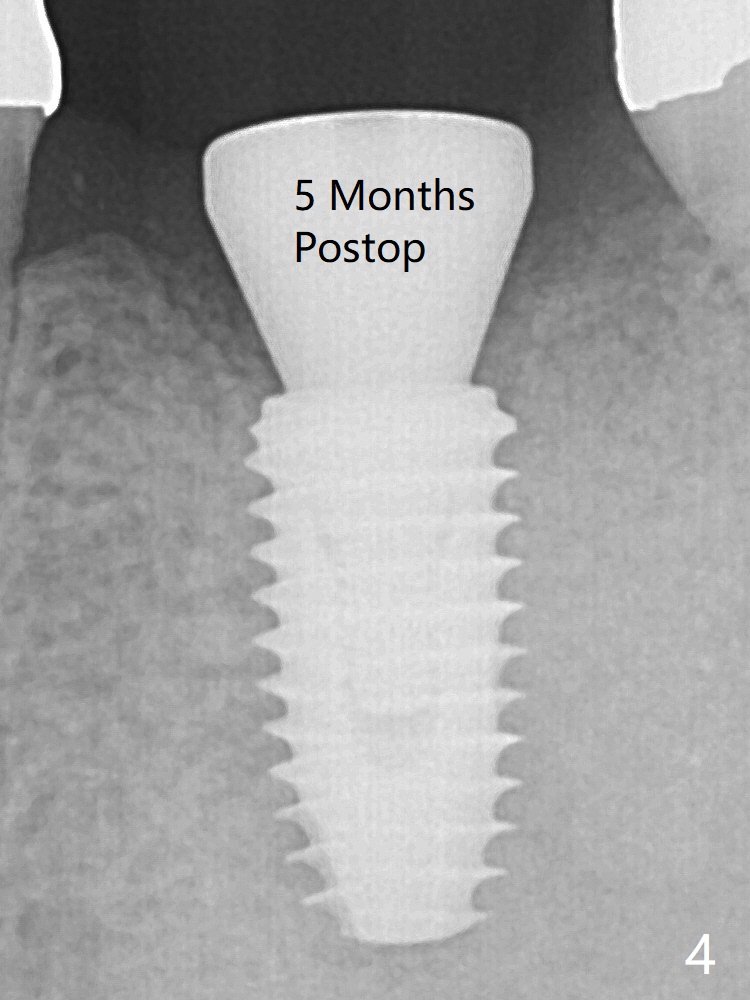

The bone is long enough to hold a 11.5 mm long implant. There is no difficulty in inserting the corresponding drill (4.5x11.5 mm) into the metal sleeve, but the lower right posterior teeth prevent the implant handpiece from going downward completely when the handpiece accesses lingually. Because of the extra manipulation, a 5x10 mm implant achieves insertion torque of ~ 20 Ncm (Fig.2). <: apical space. When the implant is placed initially according to the protocol/design, the implant is slightly supracrestal buccally. The implant is then seated apically ~.5 mm, which is unnecessary retrospectively. The bone density mesial to the implant (Fig2 *) increases 5 months postop (Fig.4), whereas that distal to the implant remains low 9 months postop (Fig.5). Bitewings taken 2.5 months post cementation (1 year postop, Fig.6,7) show subcrestal placement of the implant (advantage of guided surgery). The implant appears to be well protected; the crestal bone seems to cover the implant plateau (Fig.7 *). There will be little chance of thread exposure over years of use.